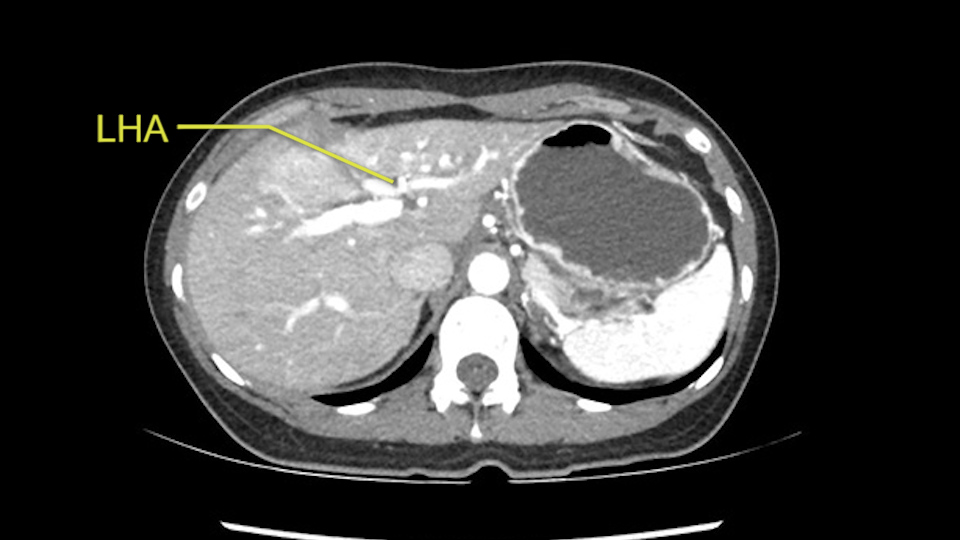

Anatomically, to plan for a left lateral segmentectomy, it’s relatively easy as far as liver surgery goes. I know that I'm going to be looking for the left hepatic vein which will be divided at some point either towards the end at the back near the vena cava or through the middle of the left lateral segment.

Inflow is not usually an issue except if there are as a replaced or aberrant left hepatic artery. In which case you’d be careful when you mobilize the left lateral segment.

So I have to say that I would do this open, not laparoscopically because of the size of the tumor itself. Upper abdominal incision. Almost certainly, we’d be able to flip this very exophytic lesion up. Intraoperative ultrasound will show the relationship of the tumor and the left portal vein but the dissection at the base of the liver, as I look at things here, I can see the left hepatic artery which sneaks up to the left of the portal vein, should be out of harm’s way so I can take the Segment 2-3 left hepatic artery. The left portal vein is somewhat compressed. But by the time you pull the liver up a bit, you’ll be able to pull that left portal vein out to length and get a good margin on it.

The other option of course is to do an anatomical left hepatectomy. In that case, I will start mobilizing of course the left lobe and try to find the ligamentum venosum, take it down and go around the left hepatic vein. I think, importantly in these cases and in this case, as you can see in the venous phase, that’s clearly a moment to stop. Because the left hepatic vein is pretty close to the middle hepatic vein as sometimes it is so you may need to dissect a little bit the parenchyma on top of the left hepatic vein to be able to go around the left hepatic vein safely.